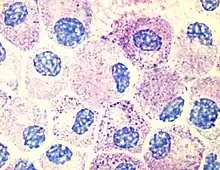

Mastcelle

En mastcelle er en celle der udskiller histamin og heparin. Det er en type granulocyt. Mastcellerne fremmer de betændelsesreaktioner, der sker ved en infektion.